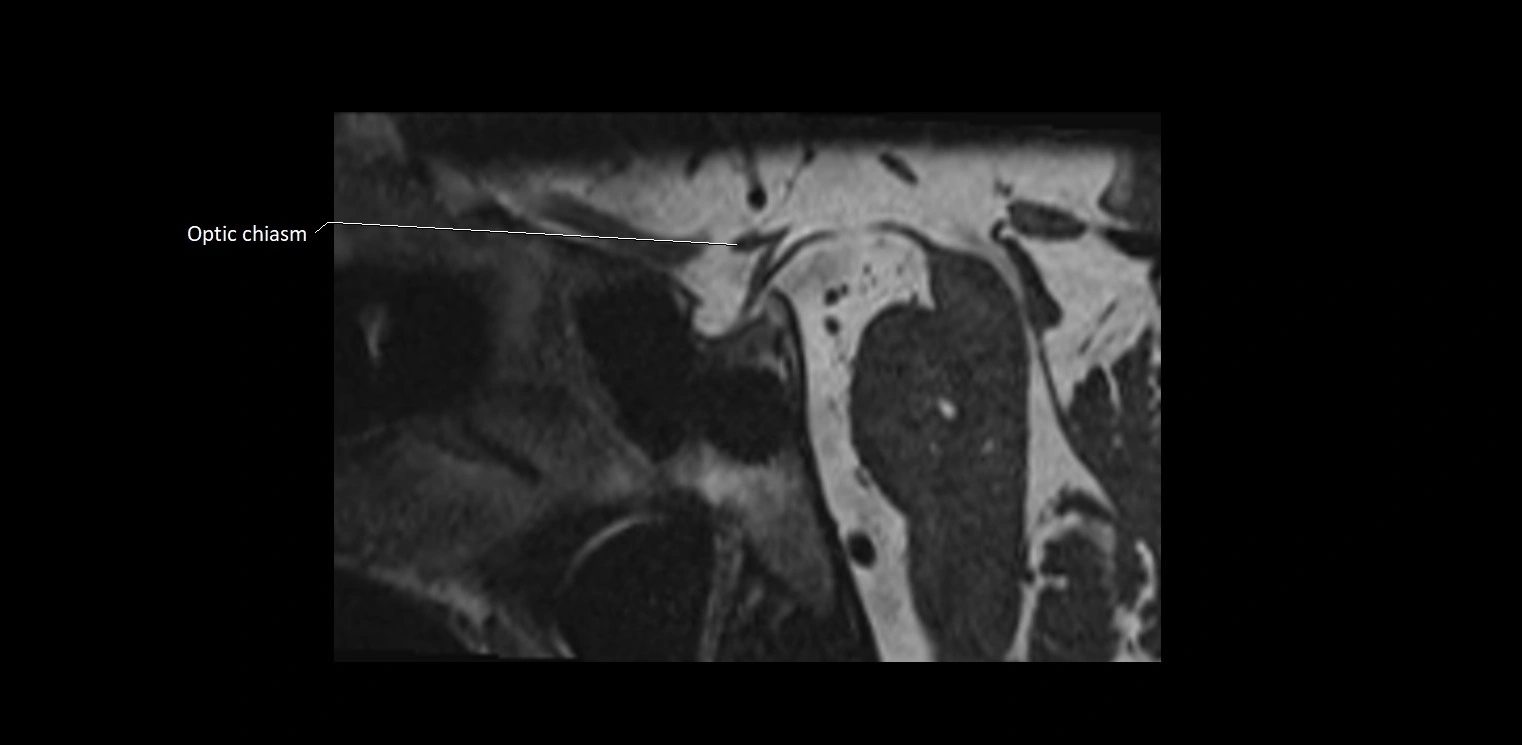

• The abducens nerve is a small, thin, linear structure

• Best visualized on high-resolution T2-weighted 3D MRI sequences (e.g., FIESTA or CISS)

• Seen as a hypointense (dark) line running from the brainstem at the pontomedullary junction, traversing the prepontine cistern, and entering Dorello’s canal under the petrosphenoidal ligament, then into the cavernous sinus, and finally the orbit